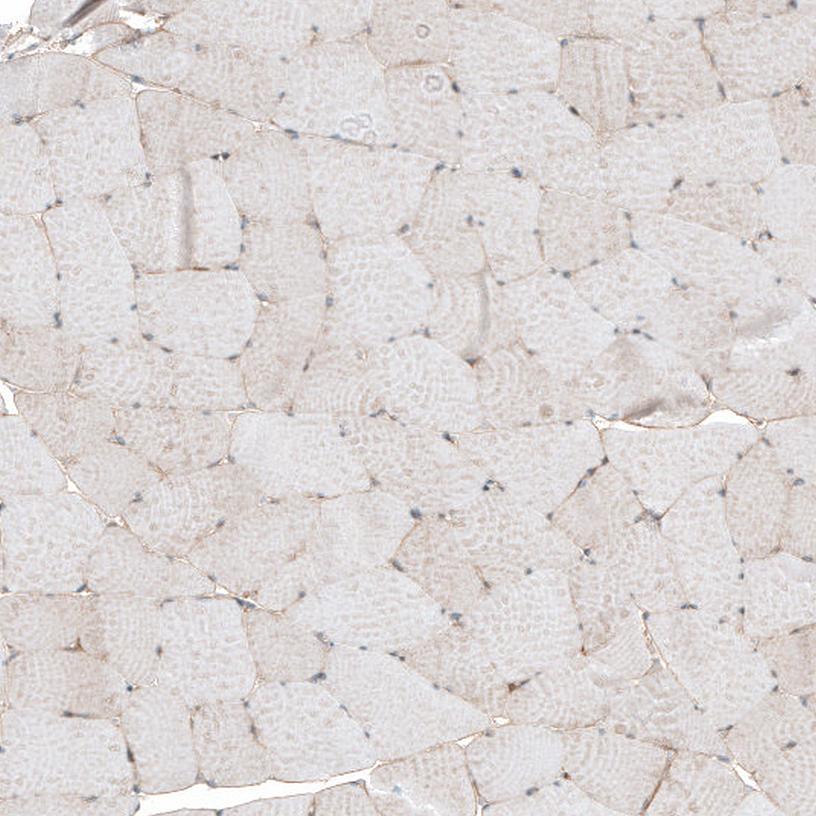

Immunohistochemical staining of human liver shows moderate to strong membranous positivity in hepatocytes.